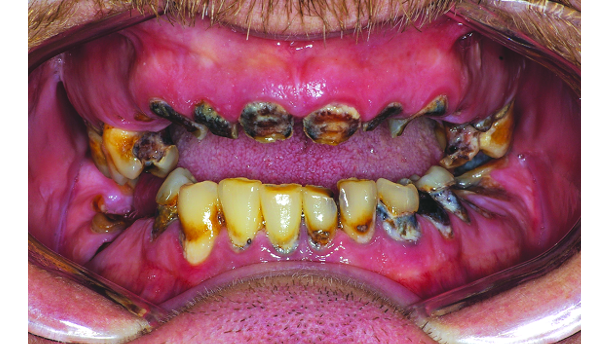

A 36-year-old male patient presented for treatment with advanced, extensive caries and localized periodontal disease (Figs. 1a–c). In addition to not having seen a dentist in more than 20 years, the patient was recovering from an addiction to methamphetamine, which had caused excessive clenching and grinding that had substantially worn down the patient’s teeth. The many years of dental neglect combined with these parafunctional habits to render the patient’s severely decayed dentition untreatable (Fig. 2). Further, the deterioration of the patient’s teeth was accompanied by significant soft-tissue recession and bone resorption.

Because of the patient’s relatively youthful age and his continued bruxing habit, eight implants were proposed for each arch in order to maximise the distribution of occlusal load, the preservation of his ridges, and the long-term prognosis of the restoration. The resorbed state of the patient’s maxillary and mandibular ridges necessitated a grafting procedure to create the foundation needed for implant placement. Custom abutments would be used to position the prostheses for optimal aesthetics. Although BruxZir Solid Zirconia Full-Arch Implant Prostheses (Glidewell Europe GmbH; Frankfurt/Main, Germany) would have been the ideal restorations given the need for long-term durability in this case, the product was not yet available at the time of treatment. Thus, PFM prostheses were chosen in order to avoid acrylic and its susceptibility to staining, wear and fracture. The proposed PFM restorations included layered pink porcelain to recreate the patient’s natural gingival contours. All aspects of treatment were explained to and accepted by the patient. The first phase of treatment began by atraumatically extracting the patient’s entire dentition using Physics Forceps (Golden Dental Solutions Inc.; Detroit, USA), which allowed for removal of the teeth without causing any damage to the surrounding bone. The extraction sockets were filled with grafting material in order to preserve the sockets and rebuild the maxillary and mandibular ridges for ideal implant placement. The patient was provided with immediate dentures, which were prefabricated based on impressions that were taken at a previous appointment (Fig. 3).